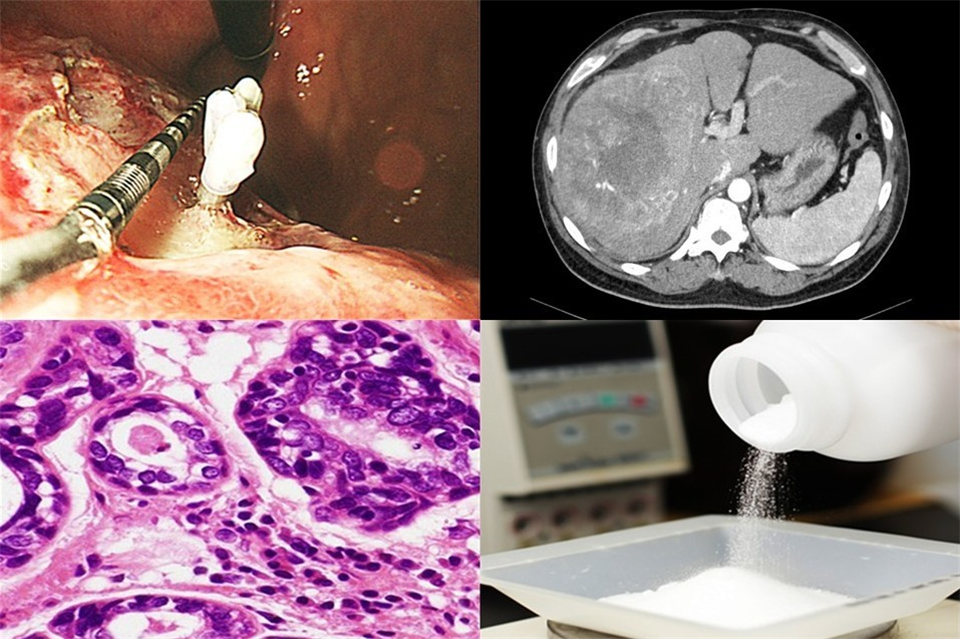

学生教育では消化管内視鏡検査・腹部超音波検査、また、それに関する治療手技を通して消化器疾患全般の病態の理解が深まるように努めています。また、OSCEやチュートリアルによる教育にも積極的に参加しています。さらに実際の入院症例を学生自身が中心となって病歴、検査所見・画像所見、治療内容などを要約し、対象疾患の病態を学習する実践臨床病態学や内視鏡モデルを使用しての模擬内視鏡検査などを含めたBedside Learning(BSL)も行っています。初期研修医教育では消化管内視鏡検査・腹部超音波検査の習得を目標に指導し、可能な限り多数の症例で実際の臨床経験を積んでもらえるように配慮しています。専門医教育では県内の学会指定教育病院等と連携して、消化器内科領域の各種専門医(消化器病、肝臓、消化器内視鏡等)の取得環境を整え、多数の専門医を育成しています。大学院教育では消化器がん免疫の病態解明、B型肝炎ウイルスの遺伝子解析と治療、血中循環腫瘍細胞の検出など多岐に渡るテーマで教育指導を行っています。